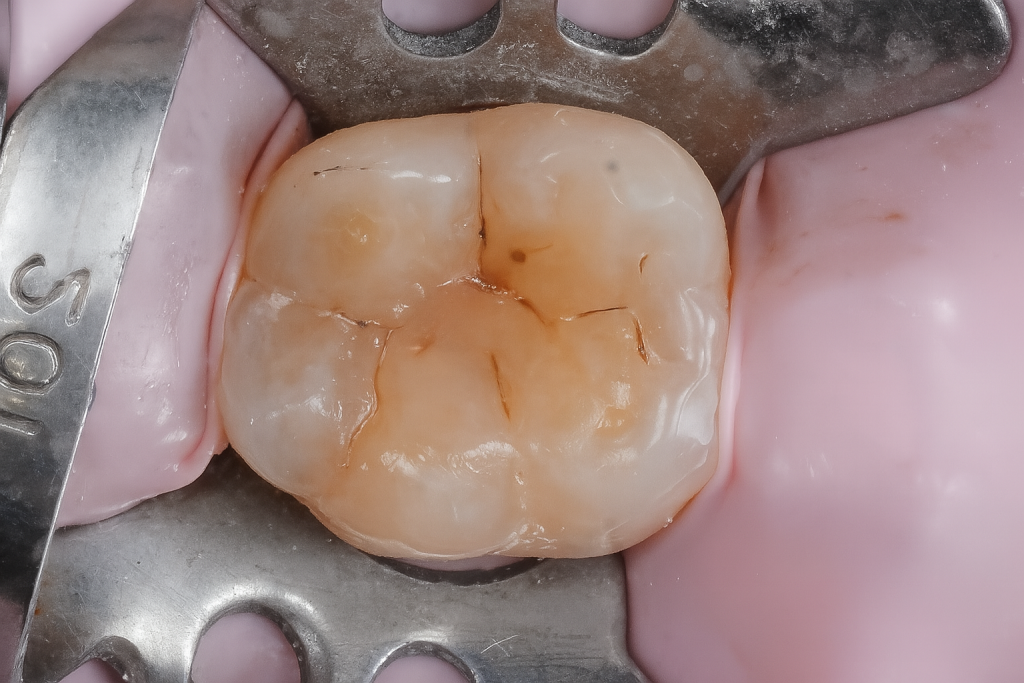

A mandibular first molar presented with localized occlusal caries (Fig 1). Under rubber-dam isolation, conservative cavity preparation was done, preserving pericervical dentin and enamel ridges. The cavity outline followed the carious extension only, minimizing healthy tissue removal.

- Fig 1: Pre-operative occlusal caries on molar.